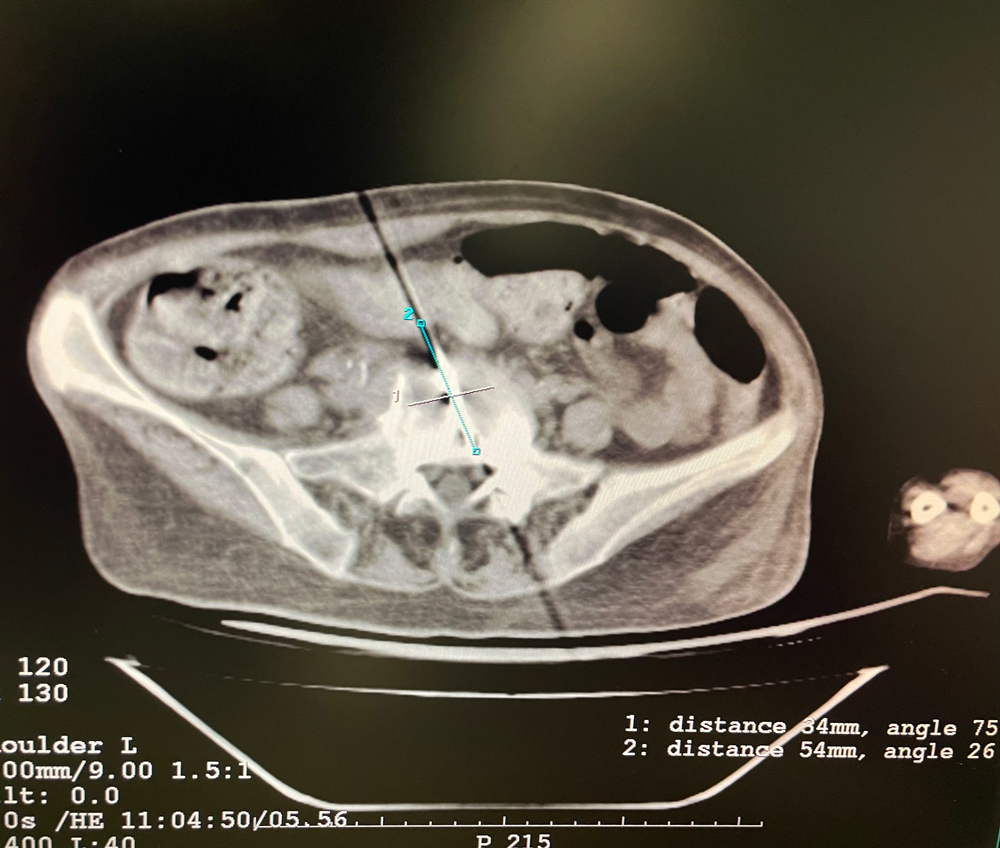

女,56岁,肺转移瘤,骶骨、左侧肋骨各一转移灶,病灶大小均为5cm。骶骨转移灶、肋骨转移灶各进行2个冻融循环。患者术后状况良好。